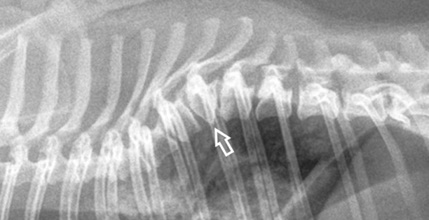

Κοιλιακή υποπλασία του σώματος του Θ8 σπονδύλου (σφηνοειδής σπόνδυλος με κορυφή κοιλιακά)

Πλάγιο ακτινογράφημα ΣΣ. Ο Θ13 είναι ραχιαίος ημισπόνδυλος ή σφηνοειδής σπόνδυλος με την κορυφή κοιλιακά.